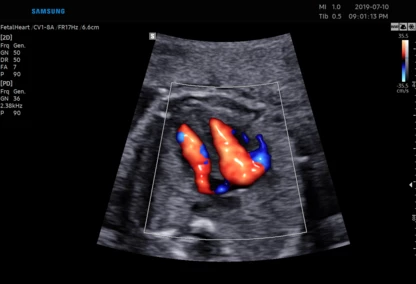

• Najnowsza generacja aparatu USG pozwala na przeprowadzanie dokładnej diagnostyki obrazowej, diagnostyki przepływów (Doppler).